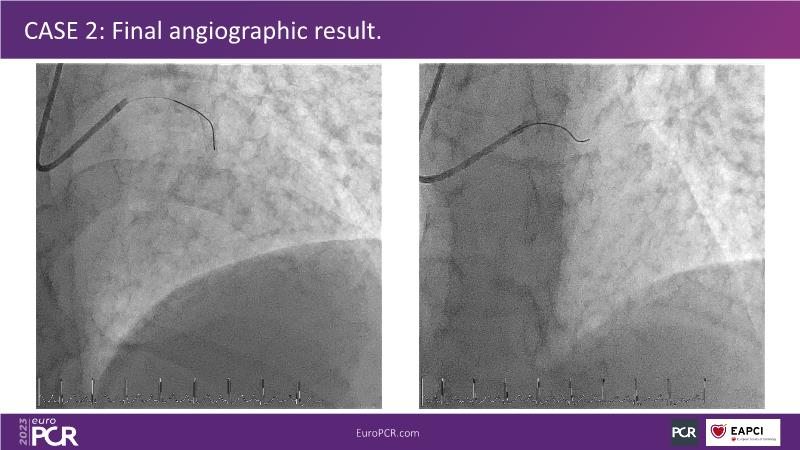

• To understand why you can count on customised drug delivery platform of DES+DCB in complex settings with imaging-based evidence through case presentations